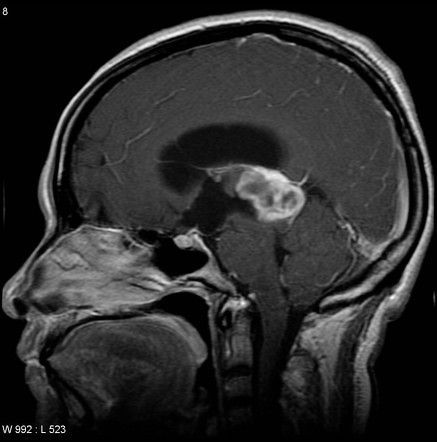

The mass in the pinealoma can be attributed to either pineal parenchymal tumor or germinomas. The pineal mass is usually asymptomatic. However, obstructive hydrocephalus or parinaud syndrome can occur as a result of pineal mass. The pineal mass can cause upward displacement of internal cerebral veins as seen on radiology. Reference: https://radiopaedia.org/articles/pineal-region-mass Image via: https://radiopaedia.org/articles/pineocytoma